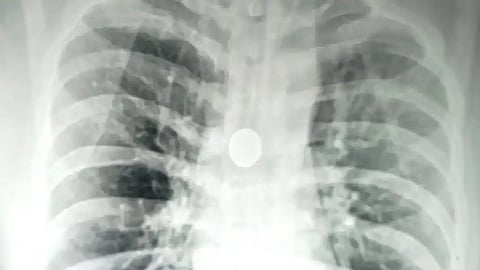

உத்தரப்பிரதேசம் வாரணாசியில் உள்ள பனாரஸ் இந்து பல்கலைக்கழகத்தின் சர் சுந்தர்லால் மருத்துவமனையில், 40 வயது மதிக்கத்தக்க நபர் ஒருவரின் மூச்சுக்குழாயில் 25 பைசா நாணயமொன்று மாட்டிக்கொண்டுள்ளது. இவர் தனது 32 ஆவது வயதில் நாணயத்தை வாயில் வைத்து உறங்கியபோது, அதனை விழுங்கியுள்ளார். ஆனால் தற்போதுதான் அதை அறிந்து மருத்துவமனையில் அனுமதிக்கப்பட்டிருக்கிறார்.

மருத்துவமனையில் அவரை பரிசோதித்த மருத்துவர்கள் மூச்சுக்குழாயில் இருக்கும் நாணயத்தை அறுவைசிகிச்சையின் மூலம் எடுக்க தீர்மானித்துள்ளனர். இதற்காக, கார்டியோ - தொராசிக் அறுவை சிகிச்சை நிபுணர் பேராசிரியர் சித்தார்த் லகோடியா மற்றும் பேராசிரியர் எஸ்.கே. மாத்தூர் தலைமையிலான மருத்துவர்கள் கொண்ட குழு கடந்த செவ்வாய் (02.07.2024) அன்று அறுவை சிகிச்சை மேற்கொண்டு மூச்சுக்குழாயிலிருந்து நாணயத்தை நீக்கியுள்ளனர்.